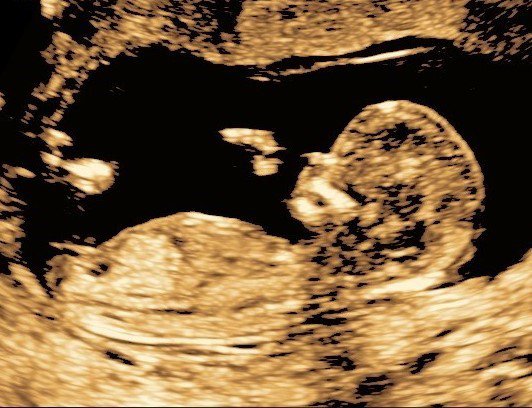

Obstetriska Ultraljudsundersökningar för alla gravida kvinnor

Alla erbjuds en ultraljudsundersökning både i vecka 11-14 samt under vecka 18-20.

Dessa undersökningar skall visa graviditetslängden, tidpunkt för beräknad förlossning samt hur graviditeten utvecklas.